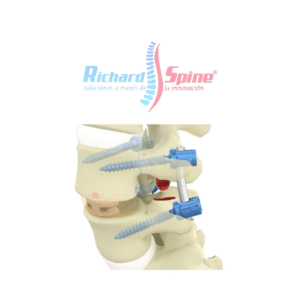

- Columna Vertebral

Placa de Fusión intercorporal cervical anterior

- La placa de fusión intercorporal cervical anterior es un dispositivo metálico utilizado en cirugía para estabilizar la columna cervical, específicamente en procedimientos de fusión intersomática anterior (ACIF). Esta placa se coloca en la parte frontal de las vértebras cervicales, después de la extirpación de un disco intervertebral dañado, para mantener la alineación y promover la fusión ósea entre las vértebras.